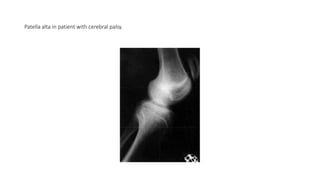

• Patella alta is common in patients with cerebral palsy (93% in one

study) and usually is associated with crouched gait (Fig)

Patella alta in patient with cerebral palsy.